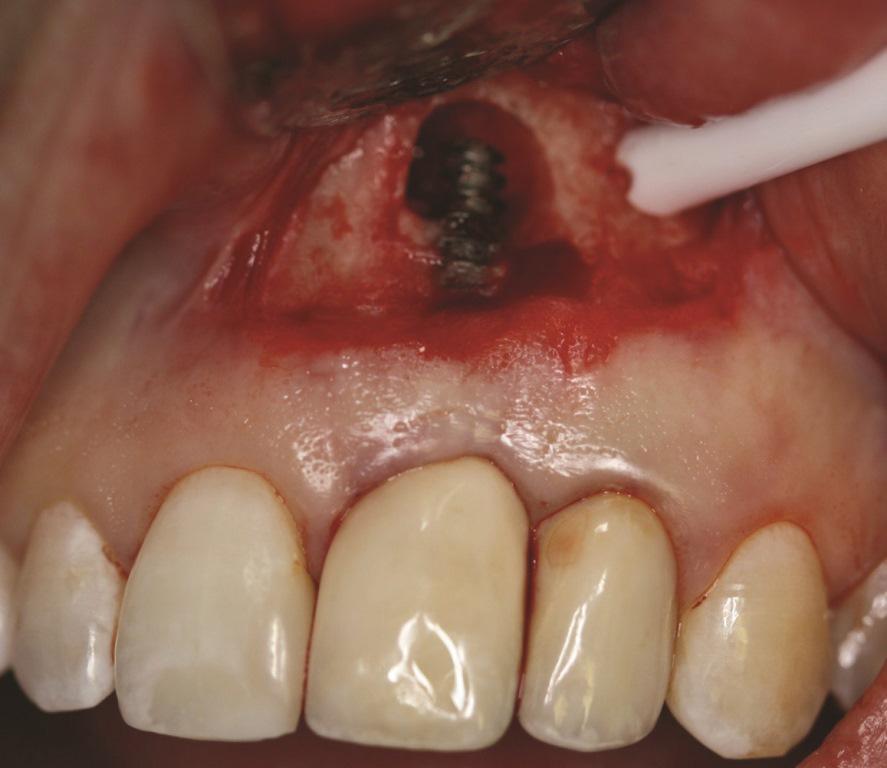

В случае 1, из-за высокой линии улыбки и асимметричной длины клинических коронок, пациентке был выполнен вестибулярный разрез в области мукогингивального соединения с отслаиванием полнослойного лоскута для доступа к верхушке имплантата. Кюретаж имплантата был выполнен титановыми кюретками и щетками (Фото 5). Поверхность имплантата обрабатывали в течение 2 минут суспензией доксициклина с физиологическим раствором. Периимплантатный дефект был заполнен гранулированным лиофилизированным костным аллотрансплантатом (ЛКА) (Фото 6) и покрыт коллагеновой мембраной (Фото 7). Первичное закрытие лоскута было достигнуто с использованием рассасывающихся швов (Фото 8).

Фото 5. Случай 1: Вестибулярный вид, показывающий периапикальную потерю кости вокруг № 2.1 после кюретажа имплантата и обработки суспензией доксициклина с физиологическим раствором.